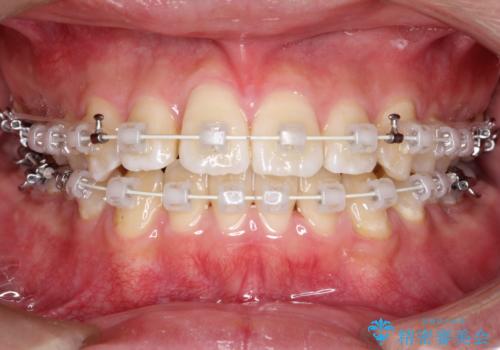

【ワイヤー矯正】前歯の凸凹を治したい。

- 前歯の凸凹を主訴に来院されました。

患者様がマウスピース矯正の使用時間に不安があるため、ワイヤー矯正にて治療を行なっております。